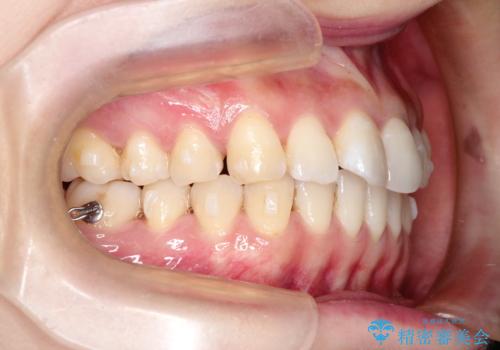

- 前歯の見た目の改善を希望され来院された患者様です。

初診時の歯並びの状態としては、上下にガタガタがある状態であり、特に上の前歯(左上1番)の捻じれを最も気にしていらっしゃいました。

口元の位置も悪くなくスペース必要量も軽度であったため、非抜歯/マウスピース矯正にて治療を行いました。

前歯の捻じれを改善するためにスペースを作る必要があり、前歯の歯の間を削って簡単に直す方法もありますが、奥歯のズレが認められたため、大臼歯後方のスペースを利用し、根本的な原因からしっかりと治療を行いました。